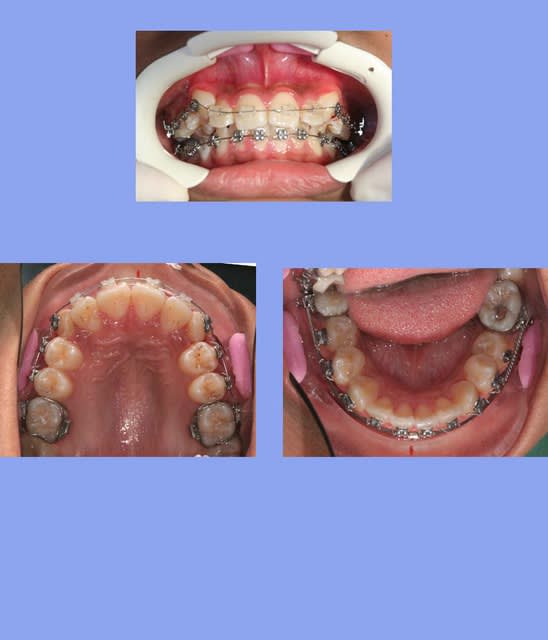

1 e3acmi - Eugenol

2 xg9czy - Eugenol

3 koixmk - Eugenol